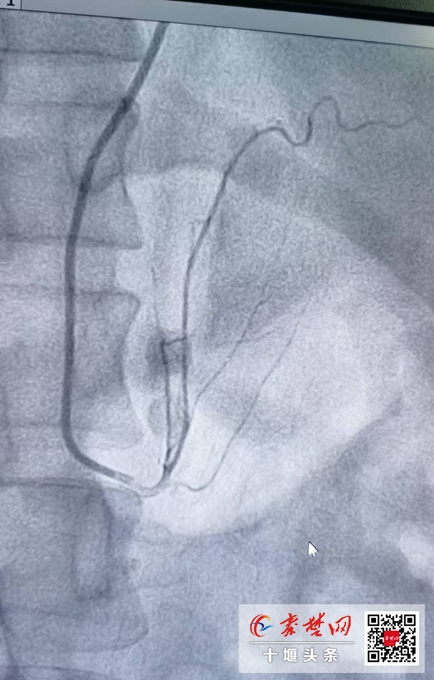

據(jù)趙繼先主任介紹,經(jīng)皮超選擇性腎上腺動(dòng)脈無(wú)水酒精栓塞術(shù)是國(guó)內(nèi)治療原發(fā)性醛固酮增多癥的最新技術(shù)。該手術(shù)為微創(chuàng)手術(shù),在患者全程清醒的狀態(tài)下進(jìn)行局部麻醉,經(jīng)橈動(dòng)脈上的一個(gè)小小針眼,精確找到病變所在的腎上腺動(dòng)脈,然后用無(wú)水酒精消超選擇性融掉腎上腺病變的位置,減少或阻斷醛固酮的產(chǎn)生,降低血壓,達(dá)到減少心臟、腦、腎臟的器官損害的目的。

手術(shù)歷經(jīng)30分鐘,在心內(nèi)一病區(qū)沈俊博士、范群雄副主任醫(yī)師、夏南博士組成的介入團(tuán)隊(duì)緊密協(xié)作下,手術(shù)順利完成。

趙繼先介紹,原發(fā)性醛固酮增多癥(primary aldosteronism,PA)是指腎上腺皮質(zhì)分泌過(guò)多的醛固酮,臨床上主要表現(xiàn)為高血壓和低血鉀。與原發(fā)性高血壓患者相比,PA患者心臟、腎臟等高血壓靶器官損害更為嚴(yán)重,因此早期診斷、早期治療至關(guān)重要。而選擇性腎上腺動(dòng)脈栓塞術(shù)(SAAE)是一種微創(chuàng)手術(shù),經(jīng)導(dǎo)管動(dòng)脈內(nèi)將無(wú)水乙醇等栓塞劑選擇性地注入到腎上腺病灶組織的供血?jiǎng)用},使之發(fā)生閉塞,中斷血供,讓病變腎上腺壞死,從而到達(dá)抑制醛固酮過(guò)量分泌的目的。

近年來(lái),SAAE成為原發(fā)性醛癥患者的新選擇,相較于外科手術(shù)花費(fèi)更少、住院時(shí)間更短,同時(shí)也可以有效避免手術(shù)切除的大部分并發(fā)癥,并且血管再通可能性少,是一種微創(chuàng)、快捷、經(jīng)濟(jì)且療效確切的治愈PA的安全有效方法。但由于腎上腺動(dòng)脈管徑較細(xì)、開(kāi)口起源變異性很大、術(shù)前難以精準(zhǔn)定位腺瘤或增生組織的供應(yīng)血管,因此,SAAE手術(shù)難度大,需要具備較高的介入技術(shù),而全國(guó)開(kāi)展此手術(shù)的醫(yī)院也并不多。